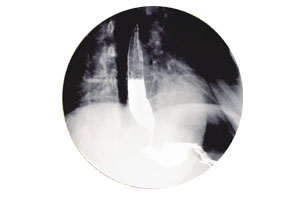

Published in La digestión